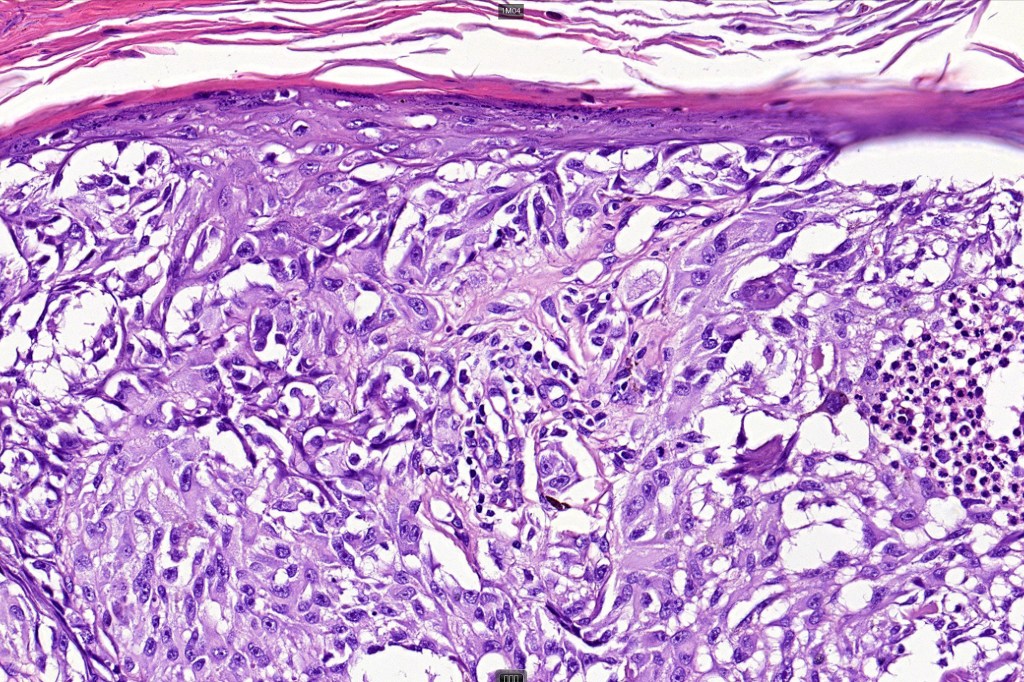

Histological features

•Involve deep dermis or subcutis

•Large nodules which often show impaired maturation

•Loss of gradient with HMB45 and Ki67

•>20% Ki67 expression